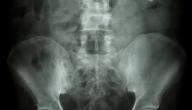

يُمكن تعريف تكلُّس المشيمة (بالإنجليزيّة: placental calcification) على أنَّه ترسُّبات بطيئة ومُستمرَّة للكالسيوم في المشيمة، وعلى الرغم من أنَّ تكلُّس المشيمة يُعتبَر أمراً طييعيّاً مع اقتراب نهاية الحمل؛ إلا أنَّه يُعَدُّ نذير خطرٍ، ودليلاً على احتماليّة حدوث تغيُّرات مرضيّة غير طبيعيّة إذا حدث قبل الأسبوع السادس والثلاثين من الحمل، وتجدر الإشارة إلى أنَّه يتمّ تشخيص تكلُّس المشيمة خلال التصوير بالموجات فوق الصوتيّة، إذ أنَّه غالباً ما يتمّ اكتشافه خلال التصوير الروتيني الذي يُجرى باستخدام الموجات فوق الصوتيّة.[٢]

يُقسّم تكلُّس المشيمة إلى عِدَّة مراحل بناءً على الأسبوع من الحمل الذي بدأ فيه التكلُّس، ويُمكن بيانها بالتفصيل كما يأتي:[٢]

- تكلُّس المشيمة المُبكِّر: يُطلَق مصطلح تكلُّس المشيمة المُبكِّر على حالة التكلُّس التي تحدث قبل الأسبوع 32 من الحمل، ويُعَدُّ تكلُّس المشيمة في هذا الوقت المُبكِّر أمراً خطيراً للغاية، وقد يتسبَّب بأضرار حقيقيّة للأم والجنين، فقد تتعرَّض المشيمة للانقطاع، ممَّا يُهدِّد بولادة مُبكِّرة، وبالتالي تعرُّض الجنين لشتَّى أنواع المخاطر المرتبطة بالولادة المُبكِّرة، كما يُمكن أن يتسبَّب بحدوث نزيف عند الأم بعد الولادة، وفي حالات نادرة جدّاً يُمكن أن يتسبَّب تكلُّس المشيمة المُبكِّر بموت الجنين داخل الرحم.

- تكلُّس المشيمة في الأسبوع 36: قد يُؤدِّي تكلُّس المشيمة خلال الأسبوع 36 من الحمل إلى ارتفاع ضغط الدم، والذي يتسبَّب بمضاعفات خطيرة، ويُعرِّض الجنين لخطر الولادة المُبكِّرة، والتي يُمكن أن تكون ولادة قيصريّة.

- تكلُّس المشيمة بين الأسبوعين 37-42: يُعتبَر تكلُّس المشيمة بحلول الأسبوع 37 من الحمل أمراً غير خطير؛ فالجنين مُكتمل، ووزنه جيِّد، وقد تحدث الولادة في أيِّ لحظة، وتجري بأمان تامّ، ومن ناحية أخرى يجب أن تتمّ الولادة قبل بلوغ الأسبوع 42 من الحمل؛ لأنَّ تكلُّس المشيمة يُضعف إمداد الأكسجين والغذاء للجنين، وهذا من شأنه أن يُلحق الضرر بالجنين.